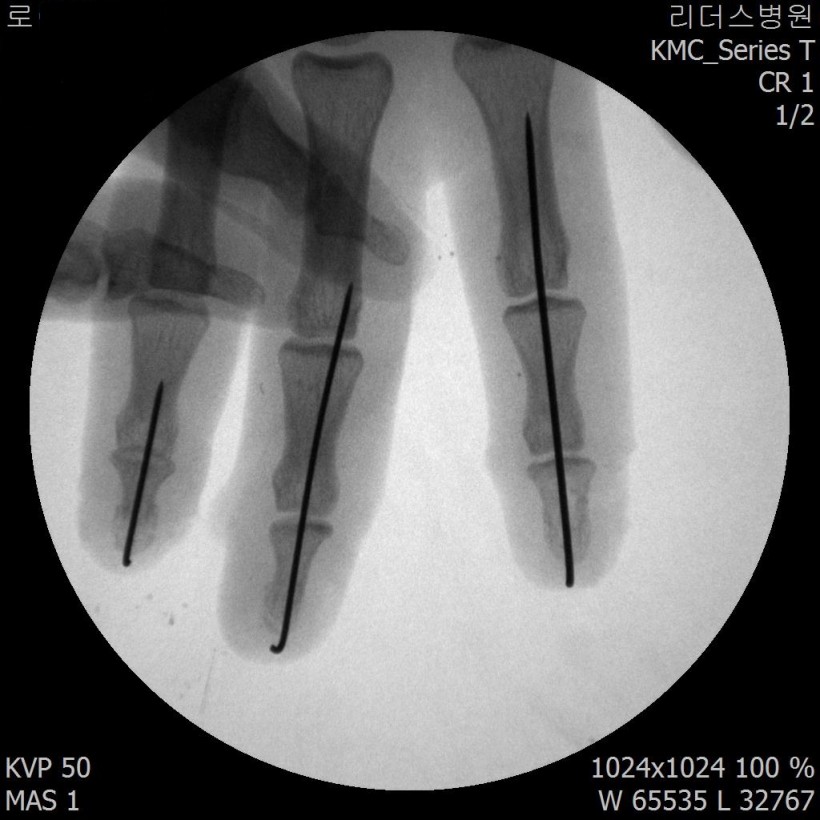

2018, 1월 1일 수지접합 ( 좌측 2,3,4수지 말단전달 치료 전, 후 모습)

2018 / 11일 당시 ( 외국인 로 **)께서 좌측 2,3,4수지 말단전달본원 방문하여